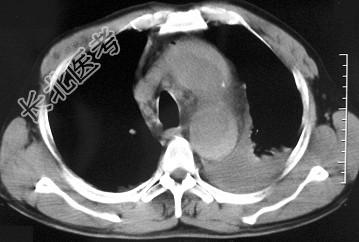

- 单项选择题男,58岁, 有高血压病史,突发胸背剧痛, CT扫描如图,其最可能的诊断为 ( )

A、主动脉瘤

B、主动脉假性动脉瘤

C、主动脉窦瘤破裂

D、高安病

E、主动脉夹层动脉瘤